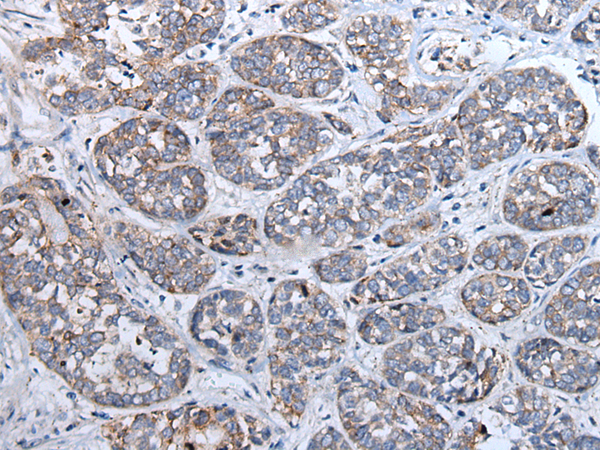

分类: 科研抗体货号: P10853别名: ALXR, HM63, FMLPX, FPR2A, FPRH1, FPRH2, FPRL1, LXA4R, FMLP-R-II应用: IHC反应种属: Human